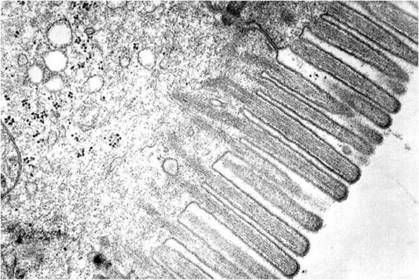

Microvellosidades

Tejido Epitelial de revestimiento, (epitelio intestinal). Prismático simple, microvellosidades en la zona apical